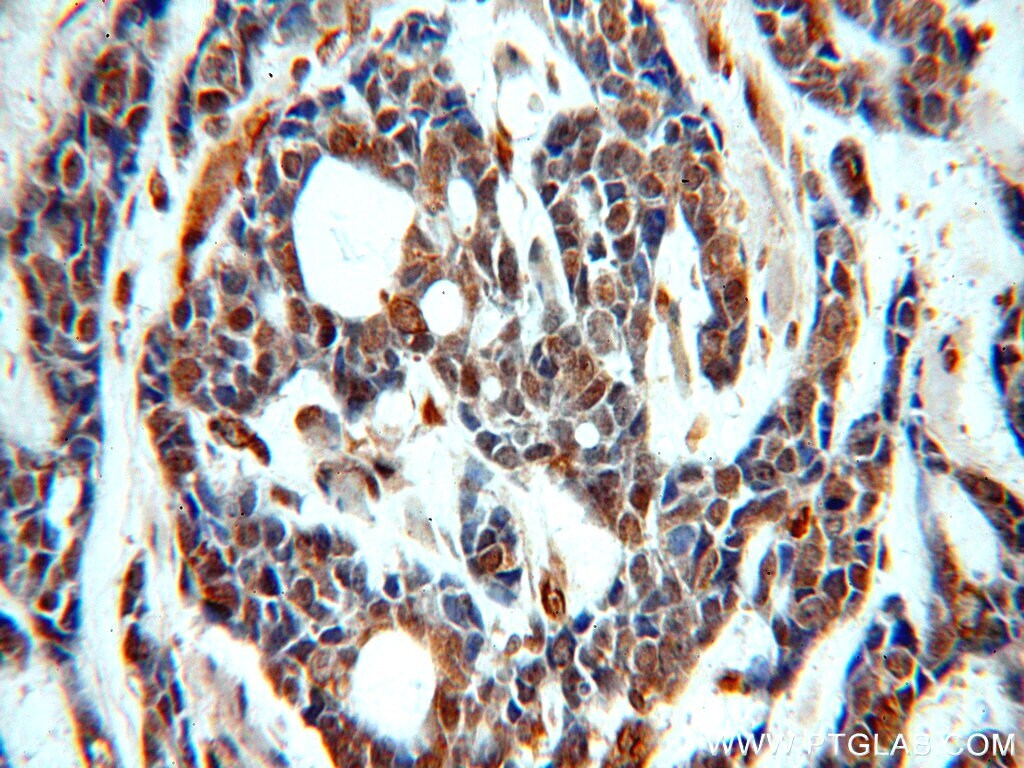

- Submitted by

- Invitrogen Antibodies (provider)

- Main image

- Experimental details

- Immunohistochemistry of paraffin-embedded human cervical cancer using 20265-1-AP (SERINC1 antibody) at dilution of 1:50 (under 10x lens).